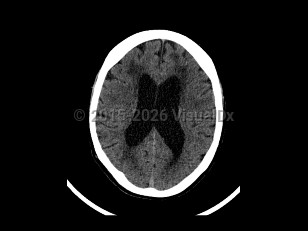

Normal pressure hydrocephalus (NPH) is a common neurologic disorder resulting in slowly progressive gait abnormalities, cognitive deterioration, and urinary incontinence.

The syndrome is often divided into 2 groups, idiopathic and secondary, based on etiology. Idiopathic NPH is thought to occur due to increased resistance to cerebrospinal fluid (CSF) absorption, leading to temporary elevations in intracranial pressure and mechanical compression of structures adjacent to the ventricles. However, the underlying etiology of idiopathic NPH has not yet been identified. Secondary causes of NPH include the sequelae of brain infections such as meningitis, trauma, or subarachnoid hemorrhage. This article will focus on the diagnosis, evaluation, and treatment of idiopathic NPH.